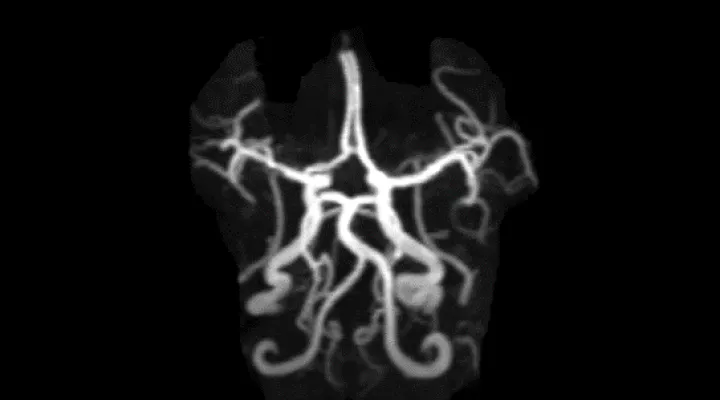

Schlaganfall, neurovaskuläre Erkrankungen

Schlaganfälle treten selten auch bei Kindern auf. Zu einer Durchblutungsstörung des Gehirns können verschiedene Erkrankungen führen wie eine Entzündung der Blutgefässe (Vaskulitis), eine Erkrankung des Herzens oder eine Störung der Blutgerinnung.

Oft kommen mehrere Faktoren zusammen. Bei Kindern ist eine rasche Abklärung und Therapie ebenso wichtig wie bei den häufiger betroffenen Erwachsenen. Als Stroke Center für Kinder arbeiten wir eng mit dem Schlaganfall Zentrum Zürich (USZ) zusammen. Die Kinder aus dem Moyamoya Center im Kinderspital werden in einem interdisziplinären Ansatz von unserer Abteilung mit betreut.